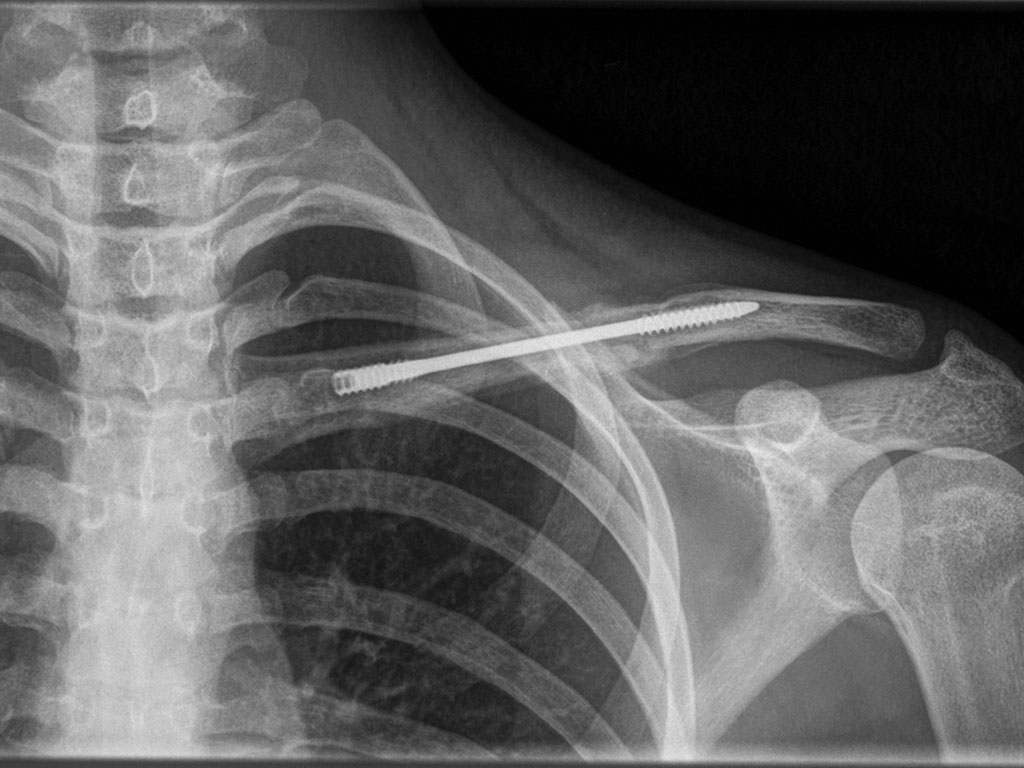

Dual-Trak Clavicle Screw System

The Acumed Dual-Trak Clavicle Screw System is a fully intramedullary solution for simple middle third clavicle fractures.

Maximum Compression

Interfragmental compression is achieved by the differential pitch on the screw’s tip and tail ends.

Screw Direction Choice

Screws can be implanted in a medial-to-lateral or lateral-to-medial direction based on need.